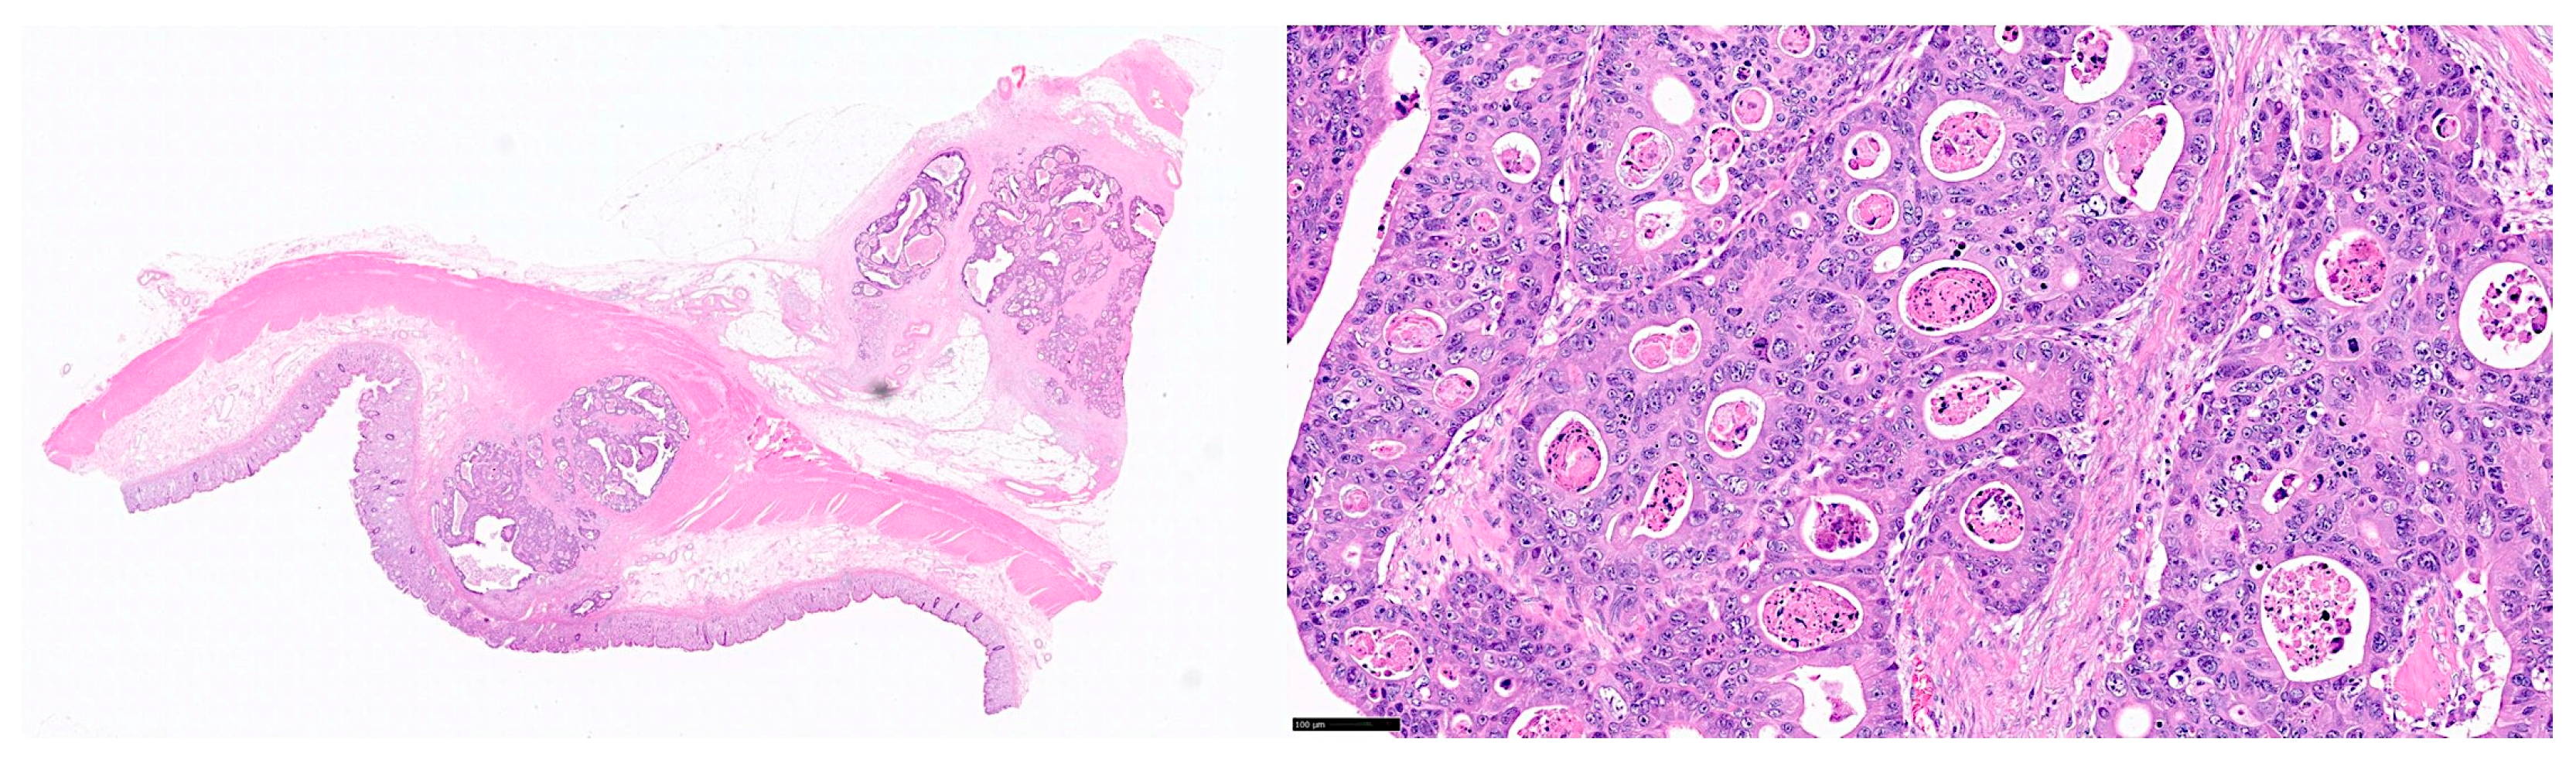

Inflammatory bowel disease (IBD) is a chronic inflammatory condition of the gastrointestinal tract characterized by the deregulation of immuno-oncology markers. IBD includes ulcerative colitis and Chron disease. Chronic active inflammation is a risk factor for the development of colorectal cancer (CRC). Deep learning is a form of machine learning that is applicable to computer vision, and it includes algorithms and workflows used for image processing, analysis, visualization, and algorithm development. This publication of Data Descriptor type, describes a dataset of histological images of ulcerative colitis, colorectal cancer (adenocarcinoma), and colon control. The samples were stained with hematoxylin and eosin (H&E), and immunohistochemically analyzed for LAIR1 and TOX2 markers. The methods used for collecting and producing the data, analysis using convolutional neural networks (CNNs), where the dataset can be found, and information about its use are also described.